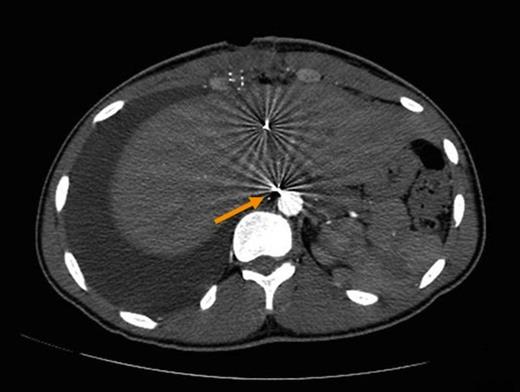

Six days later, the patient returned to the emergency department with complaints of right sided chest pain and worsening dyspnea. A plain chest film was performed (Figure 2) and demonstrated a large right pleural effusion. Computerized tomography of the abdomen also demonstrated several tiny retained metallic fragments embedded within the liver and retroperitoneum (Figure 3). A chest tube was inserted on the right side and immediately drained 2.2L of milky fluid (Figure 4).

Computerized tomography of the abdomen demonstrating tiny metallic fragments within liver. Fragment adjacent to aorta suspected of injuring retroperitoneal thoracic duct (arrow).